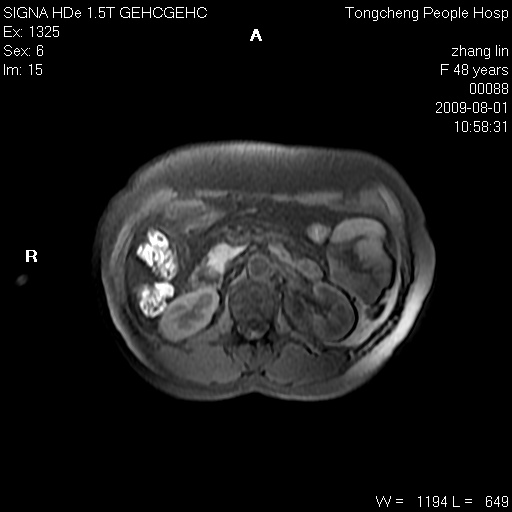

女,48岁。健康体检,彩超发现右肾占位性病变。平素健康。

临床诊断:右肾占位性病变,性质待定(囊肿?肿瘤?)。

上中腹部mr平扫+增强扫描,图像如下:

右肾上极见一类圆形病灶,t1wi呈等信号t2wi呈等高混杂信号,三期增强无强化,边界清---考虑囊肿出血。

同反相位均表现为等信号,病变无强化,考虑含蛋白的囊肿可能,弥散加权相或许有些帮助,